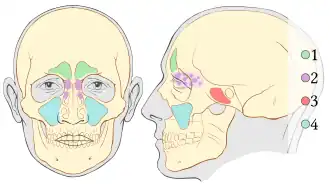

Paranasal sinuses are a group of four paired air-filled spaces that surround the nasal cavity.[1] The maxillary sinuses are located under the eyes; the frontal sinuses are above the eyes; the ethmoidal sinuses are between the eyes, and the sphenoidal sinuses are behind the eyes. The sinuses are named for the facial bones and sphenoid bone in which they are located. The role of the sinuses is still debated.

Humans possess four pairs of paranasal sinuses, divided into subgroups that are named according to the bones within which the sinuses lie. They are all innervated by branches of the trigeminal nerve (CN V).

- The maxillary sinuses, the largest of the paranasal sinuses, are under the eyes, in the maxillary bones (open in the back of the semilunar hiatus of the nose). They are innervated by the maxillary nerve (CN V2).[2]

- The frontal sinuses, superior to the eyes, in the frontal bone, which forms the hard part of the forehead. They are innervated by the ophthalmic nerve (CN V1).[2]

- The ethmoidal sinuses, which are formed from several discrete air cells within the ethmoid bone between the nose and the eyes. They are innervated by the ethmoidal nerves, which branch from the nasociliary nerve of the ophthalmic nerve (CN V1).

- The sphenoidal sinuses, in the sphenoid bone. They are innervated by the ophthalmic and maxillary nerve (CN V1 and V2).[2]

Paranasal sinuses